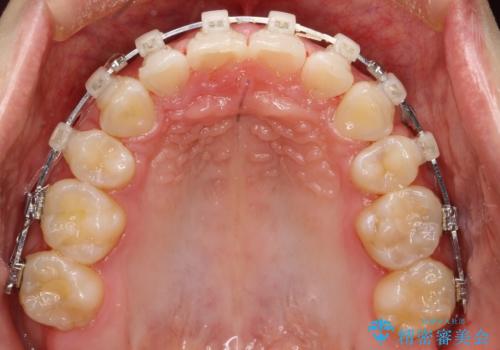

出っ歯の矯正 抜歯をしてしっかり引っ込めるワイヤー矯正

- 矯正装置

- 審美装置

- 治療計画

- 出っ歯を気にして来院されました。

しっかり前歯を下げるために抜歯を合計3本行いワイヤーにて矯正を行う計画としました。